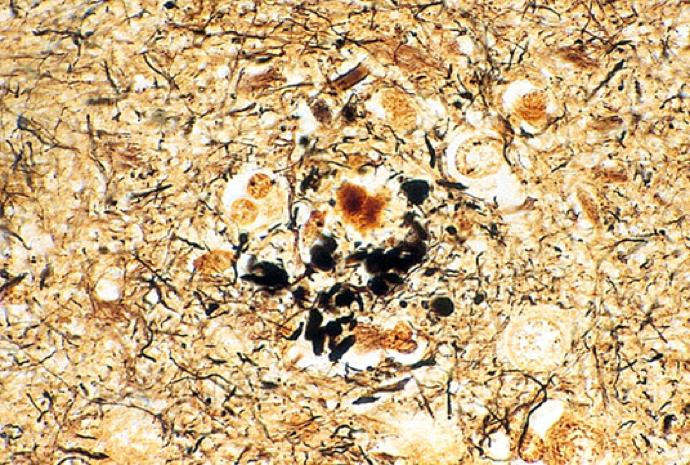

Confusion, 70, autopsy - diagnosis?

Alzheimers Disease

This is an amyloid plaque. Look at the big, swollen black neurities! Those are filled with amyloid protein aggregates.